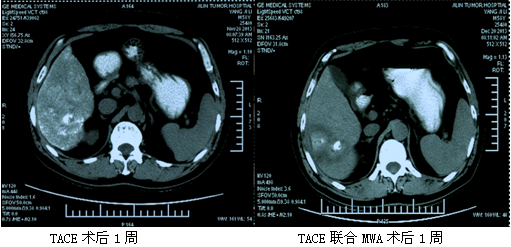

典型病例:杨XX,男,67岁,原发性肝右叶癌(BCLC B期)。给予TACE治疗1次,术后2周联合微波射频消融术1次复查CT见消融环明显,肝内病灶坏死充分。

典型病例:宋XX,男,63岁,确诊原发性肝右叶癌术后(BCLC B期)5年,入院给予TACE治疗3次,末次TACE术后联合微波消融1次后疼痛症状明显减轻,病灶明显萎缩。